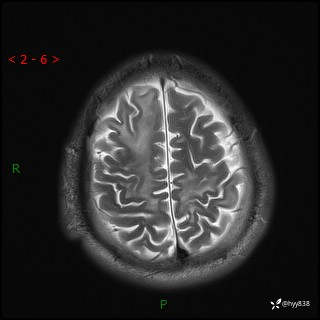

辅助检查:MRI

MRI T2WI